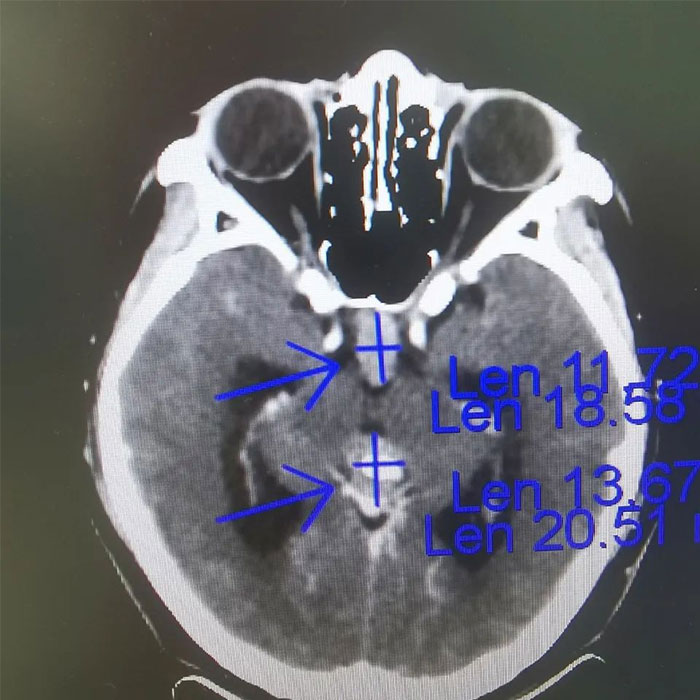

▲ 放療前病灶影像定位

在當?shù)蒯t(yī)院行MRI檢查提示:鞍區(qū)及松果體區(qū)異常信號,幕上腦積水,右側(cè)乳突少許炎癥。9月,患者在外院行經(jīng)蝶竇鞍區(qū)病損切除術(shù),術(shù)后病理示:生殖細胞瘤。